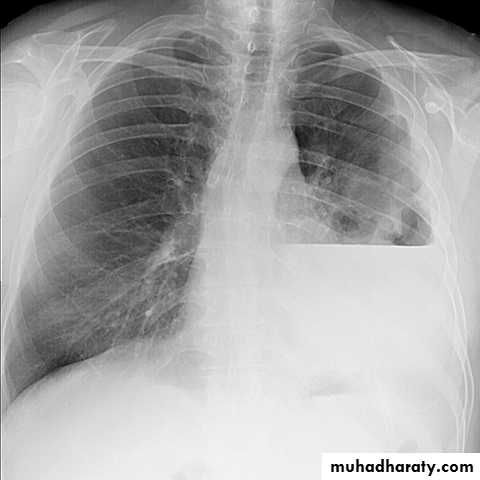

Empyema

EmpyemaX-ray Empyema